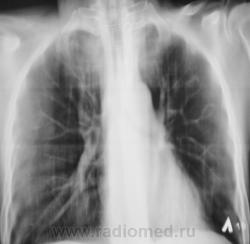

Следущий "контроль".

А сейчас, если не ошибаюсь, есть свежие очаги слева?

Я тоже отметил "свежие" очаги, но они появились на "фоне" курса лечения.